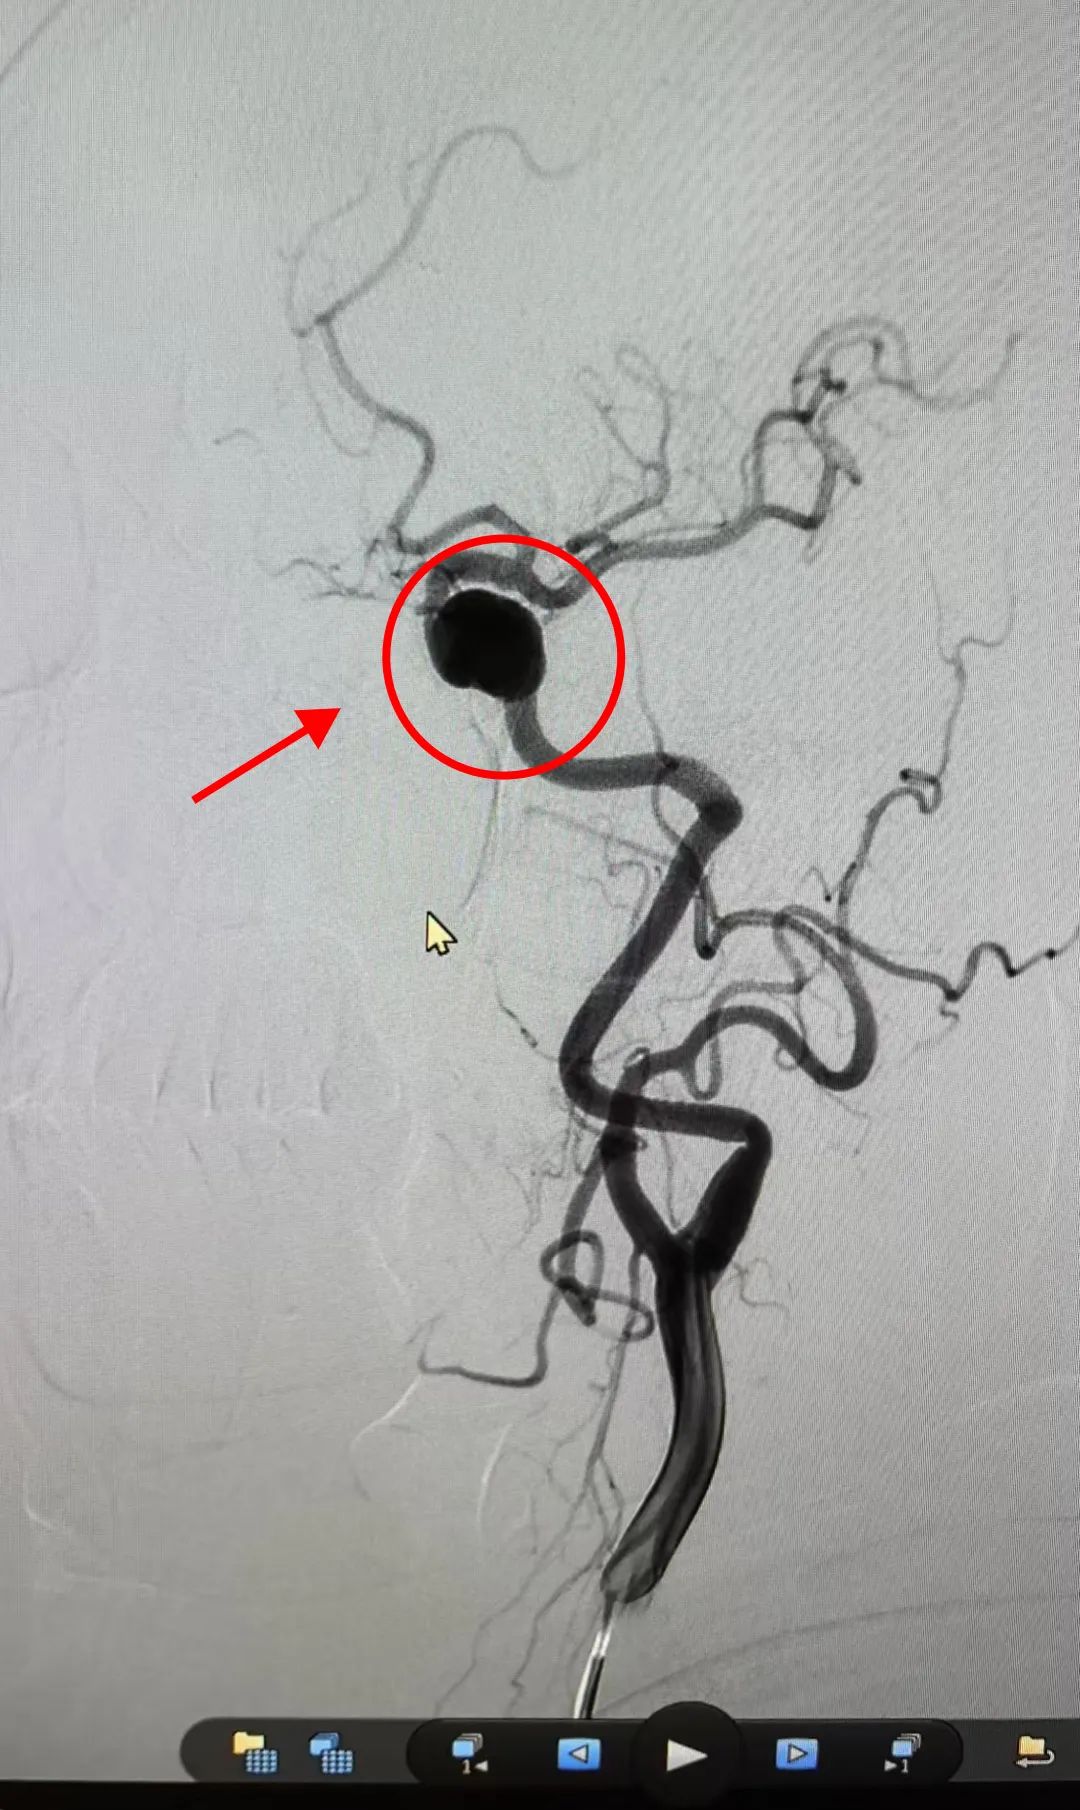

通过进一步脑血管造影(DSA)检查,明确为颈内动脉海绵窦段大型动脉瘤(尺寸1.9cm×1.2cm×1.0cm,瘤颈宽1.0cm)。此类动脉瘤因体积大、位置深,且伴有高血压,破裂风险较高,需要积极治疗处理

术后造影显示动脉瘤完全闭塞,患者表示头痛症状得到缓解,目前已顺利出院。